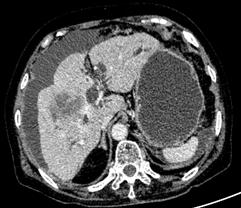

2.肝门型及远端型胆管细胞癌

病变区胆管壁增厚,管腔狭窄,伴上游胆管扩张。

•  CT:胆管浸润狭窄型胆管癌动脉期明显强化,外生型胆管癌门脉期强化更显著。

•  MRI:信号特征反应肿瘤组织成分,纤维成分越多,T2WI信号越低,粘液及坏死组织越多,T2WI信号增加,肿瘤无薄膜,增强呈渐进性强化。

肝内胆管细胞癌     肝外胆管细胞癌

病理提示①为肝内胆管细胞癌,②肝外胆管细胞癌